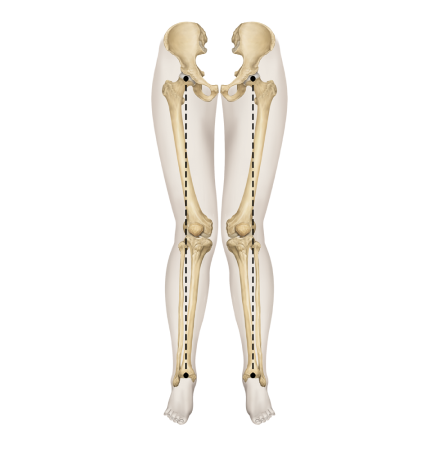

다리의 휜 모양에 따라

▲ O자 다리

▲ X자 다리

▲ 정상 다리

휜다리의 대표적 유형 2가지

O다리

• 무릎이 외측으로 벌어지면서 다리 축이 변형됨

• 체중부하가 다리 안쪽(내측)에 집중되어 내측 관절의 압력증가로

무릎관절의 퇴행성 변화와 통증을 초래

• 허벅지 안쪽 근육이나 엉덩이 근육이 약화되면 무릎 안정성이 떨어져 내반슬이 악화

• 기전

• 방치시

• 악화요인

X다리

• 무릎이 안쪽으로 모이면서 다리 축이 변형됨

• 체중 부하가 다리 바깥쪽에 집중되어 외측 관절의 압력증가로

무릎 통증, 불안정성, 관절 손상을 유발할 수 있음

• 허벅지 바깥쪽 근육이 과도하게 발달하고 안쪽 근육이 약화되면 외반슬이 진행

휜다리는 단순히 무릎 사이 간격이 벌어진 것이 아닙니다.

무릎 위의 대퇴골과 아래의 정강이뼈가 회전하면서 무릎까지 뒤로 빠지기 때문에 다리사이 간격이 넓어지는 겁니다.